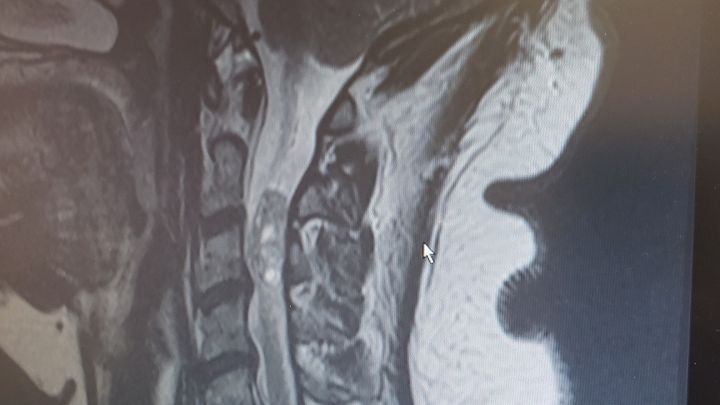

My mother had an MRI done in July and it was discovered that she had a tumor inside her spinal column and it was pressing on her nerves and its causing her massive amounts of pain. She cant sleep, barely eat, isnt recommended to work and now she cant drive. Her surgery is on the 13th of September, anything will help, please.